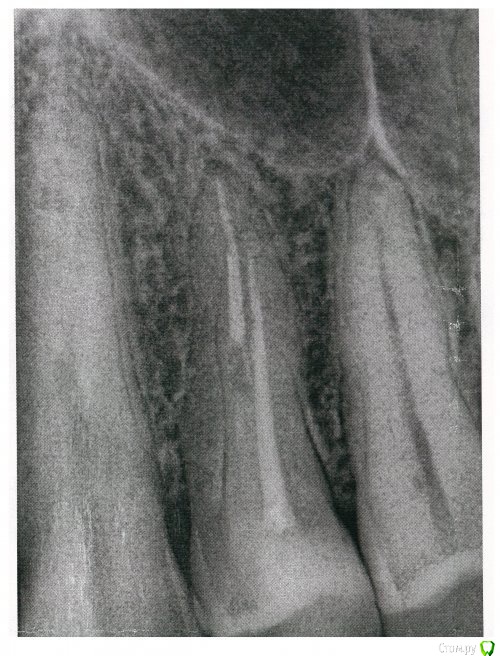

shurkne Опубликовано 2 апреля, 2015 Автор Поделиться Опубликовано 2 апреля, 2015 добавил снимок Ссылка на комментарий

shurkne Опубликовано 2 апреля, 2015 Автор Поделиться Опубликовано 2 апреля, 2015 (изменено) в 1ом канале штифт стекловолоконный Изменено 2 апреля, 2015 пользователем shurkne Ссылка на комментарий

red_butler Опубликовано 2 апреля, 2015 Поделиться Опубликовано 2 апреля, 2015 по снимку все нормально. Нет проблем с забиванием пищи между зубов? Ссылка на комментарий